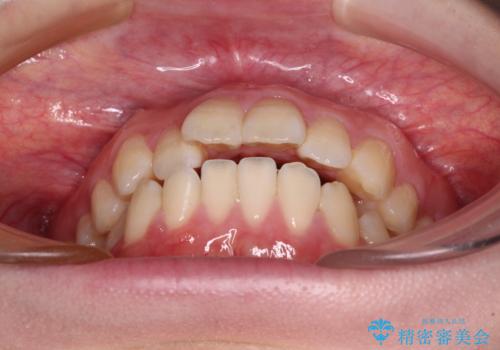

強い舌の突出癖により、上下前歯が前方に飛び出しており、特に上顎前歯は下顎よりも更に前方に位置している状態でした。

口元の突出感が改善されてことで、下唇に引っかかっていた上顎前歯も気にならなくなりました。